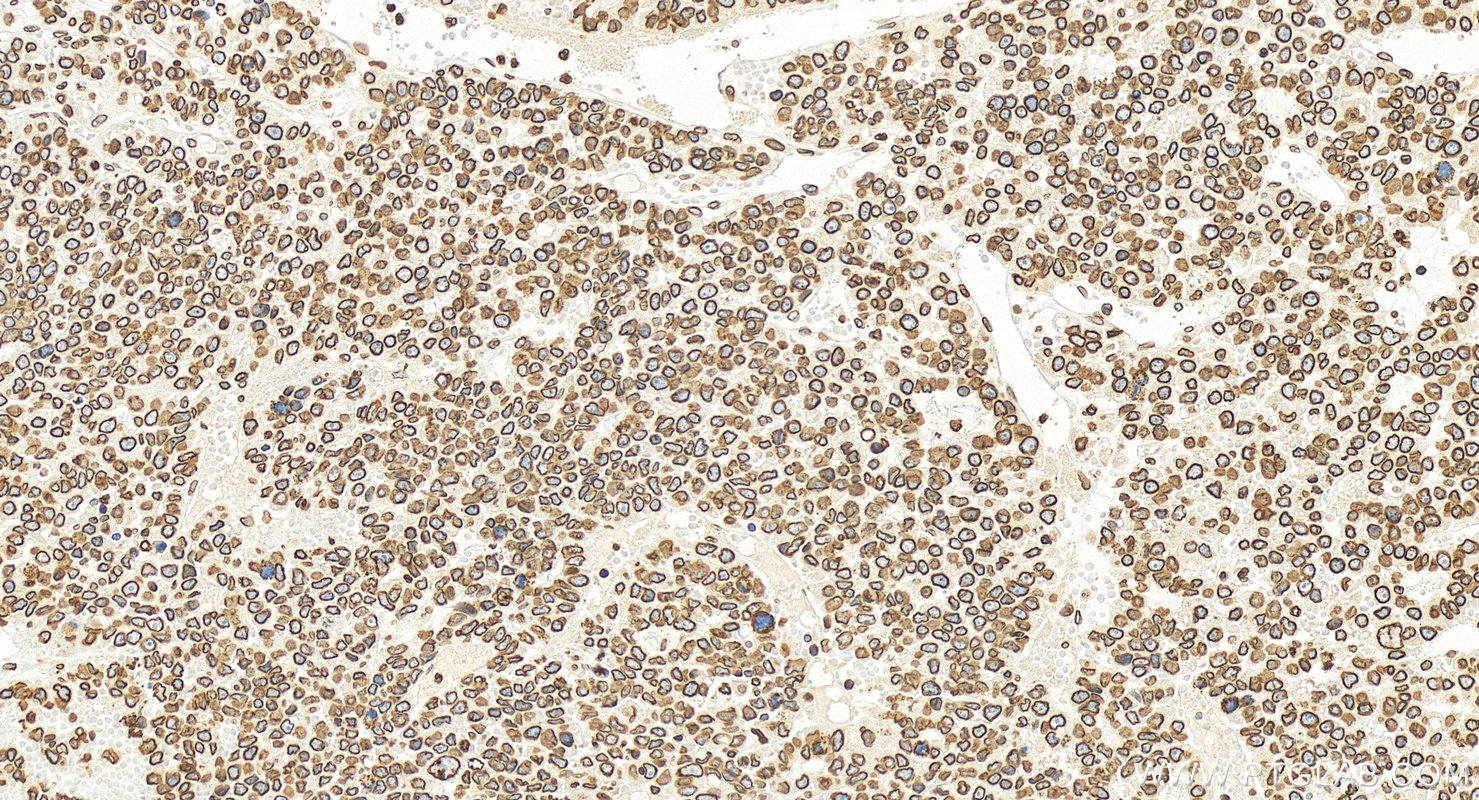

| Positive IHC detected in | mouse heart tissue, human colon tissue, human colon cancer tissue, human hepatocellular carcinoma, mouse kidney tissue Note: suggested antigen retrieval with TE buffer pH 9.0; (*) Alternatively, antigen retrieval may be performed with citrate buffer pH 6.0 |

| Immunohistochemistry (IHC) | IHC : 1:1000-1:4000 |